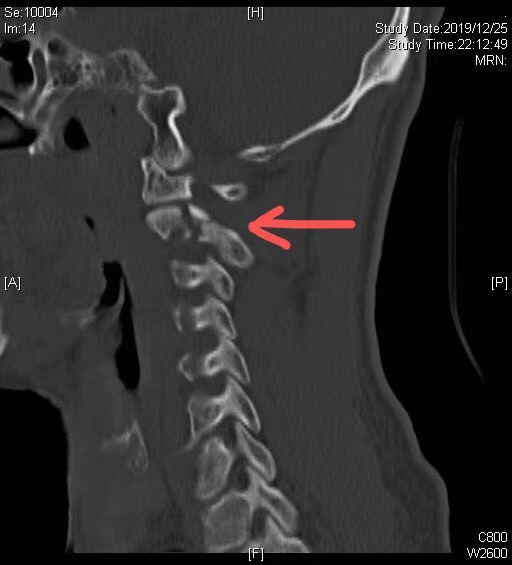

患者刚过知天命之年,车祸导致其第二颈椎(枢椎)多发骨折,骨科肖嵩华主任医师评估患者情况后,认为该骨折累及枢椎的椎弓根、椎板及附件,属于不稳定性骨折,具备内固定的手术指征,然而该患者损伤部位较高,紧邻生命中枢,且骨折块细小,对螺钉置入的精度要求极高(误差容错小于1mm),手术难度较大。“如果采用传统的手术方式,手术需要从颈后部位开大口子,创伤较大,对患者的恢复不利。”胡冬医师说道。为使患者能够更快康复,肖嵩华决定使用天玑机器人为患者进行手术。

患者骨折影像图,箭头部位为骨折位置